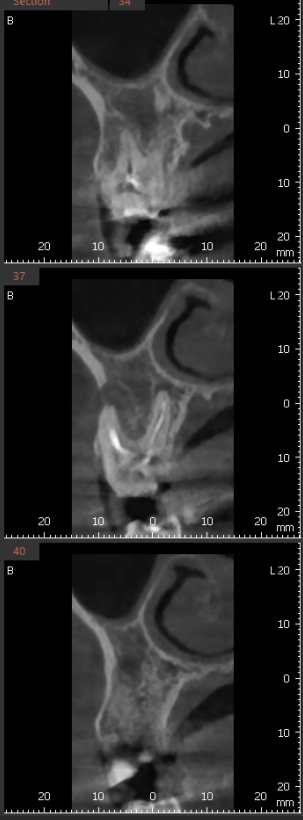

x-ray를 봐서는

염증이 없어진건지 잘 모르시겠죠~?

변화가 된 모습만 비교해드릴께요~

뿌리 절반 이상 염증들이

3달의 치료과정을 통해

손톱만큼 줄어들었습니다.

이제 뿌리 끝 까만 부분

거의 보이지 않습니다.

염증이 남아있으면 제대로 뼈가 차지 않는대요.

깨끗하게 염증이 없어졌기 때문에

까맣게 녹아 버린 뼈가

다시 하얗게 채워진 모습을 볼 수있네요~